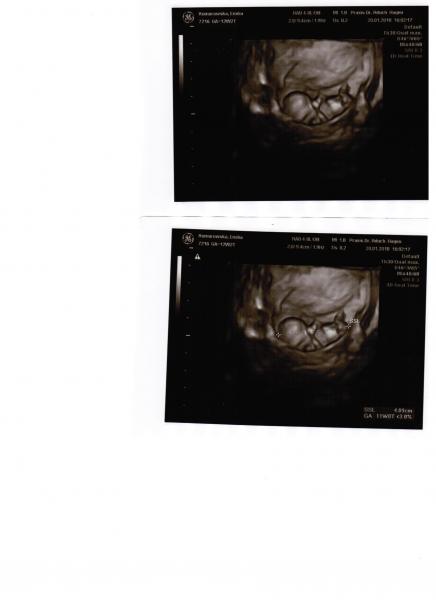

Opis zdjęcia: 11tydzien:)